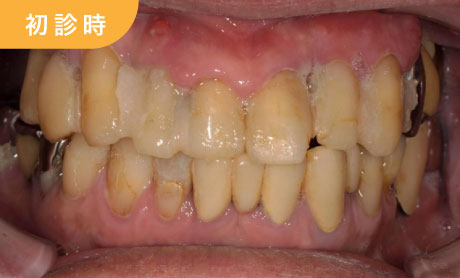

病的な歯肉

残りの歯も歯を支える骨が無いので、動揺が著しい状態です。